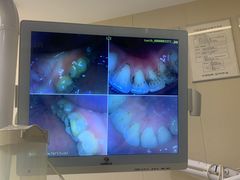

• 好大夫口腔(广州店)

• -好大夫口腔(广州店)

jiaoshen君君 | 23-11-17

报错